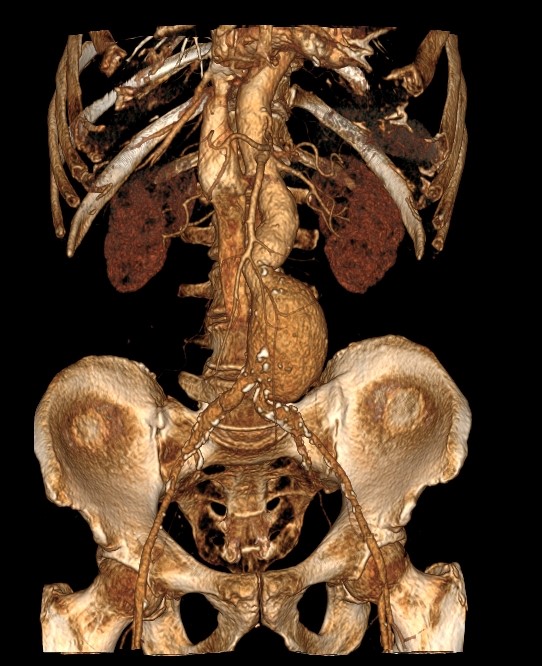

Для детальной визуализации мягких тканей используются контрастные вещества, позволяющие выявить даже незначительные структурные мягкотканные изменения. Контрастные вещества, зачастую применяются на основе бария и йода, которые по своим фармакологическим и химическим свойствам, не могут накапливаться в организме. Максимально допустимый неблагоприятный эффект, который возможен, это наличие после исследования кожного зуда, запора и поноса.